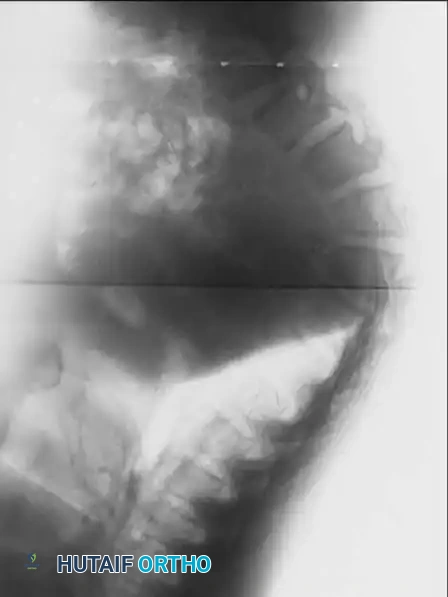

Radiographic representation of the classic thoracolumbar kyphosis seen in mucopolysaccharidoses, highlighting the anterior beaking and platyspondyly.

Detailed view of the dysplastic vertebral segments in MPS, demonstrating the thick, bulging intervertebral discs that contribute to the structural collapse.

Advanced imaging of the cervical and upper thoracic spine in a patient with mucopolysaccharidosis, utilized to evaluate for odontoid hypoplasia and spinal canal stenosis prior to surgical intervention.